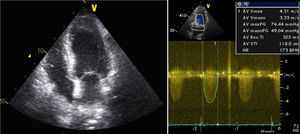

O ecocardiograma transtorácico (Figura 1) mostrou ventrículo esquerdo não dilatado, com ligeira hipertrofia do septo interventricular, com boa função sistólica global (FSG) e segmentar; válvula aórtica fibrocalcificada com gradiente transvalvular máximo de 74 e médio de 49mmHg e área calculada por equação de continuidade de 0,77cm2.

O ECG evidenciou taquicardia sinusal, com acentuação do infradesnivelamento de ST (2mm) na parede lateral. O ecocardiograma revelou acinésia apical com compromisso moderado a grave da FSG, com gradiente valvular aórtico médio de 44mmHg. Analiticamente, verificou-se subida da troponina i (12ng/mL) e agravamento da função renal.

O doente teve alta ao 24.° dia de internamento, em classe NYHA II. No ecocardiograma transtorácico à data de alta apresentava compromisso moderado a grave da FSG (Figura 4), gradiente valvular aórtico médio de 31mmHg e área valvular de 1,06cm2. Programou-se cirurgia cardíaca, após cumprimento de um mês de dupla antiagregação plaquetar.

A suspensão de noradrenalina foi realizada em menos de 24h. Contudo, o doente manteve quadro de ICA, dificultando o processo de extubação, com várias tentativas sem sucesso. Ao oitavo dia de internamento, foi decidida terapêutica com levosimendan em perfusão (sem dose de carga, dose de manutenção de 0,1mcg/kg/min), que decorreu sem intercorrências. Houve melhoria clínica significativa, com extubação cerca de 24h depois. O ecocardiograma evidenciou melhoria da função ventricular esquerda (fração de ejeção de 40%), com gradiente valvular aórtico médio de 47mmHg.